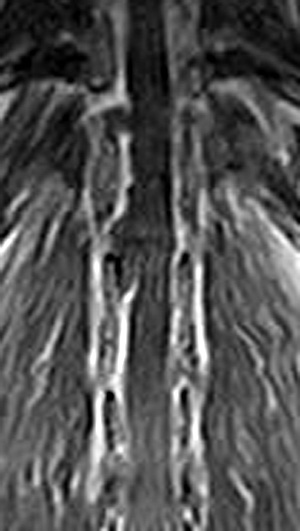

市内の先生からダックスちゃん両後肢麻痺グレード5でMRI検査及び手術依頼でご紹介がありました。MRI検査で第13胸椎-第1腰椎間椎間板ヘルニア、右側優位な圧迫と診断し手術となりました。→<その2>へ続く